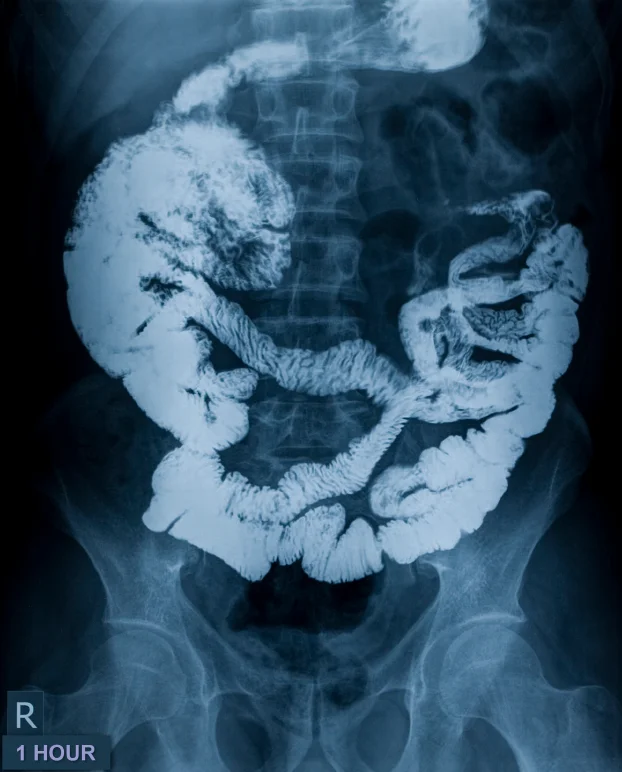

/March is colorectal cancer awareness month. Colon cancer is the second leading cause of cancer-related deaths in the United States. About 90 percent of cases occur in people aged 50 or older. And on average, the risk of developing colon cancer is about 1 in 20. However, this may vary depending on individual risk factors. Early detection is key. With regular screening, colon cancer can be found early. This is when treatment is most effective.

The best way to reduce your risk for colon cancer is to get screened regularly. The U.S. Preventive Services Task Force and the Centers for Disease Control and Prevention recommends that people start screening for colon cancer at age 50. Screening includes using high-sensitivity fecal occult blood testing, a sigmoidoscopy, or a colonoscopy. Screening should continue until age 75.